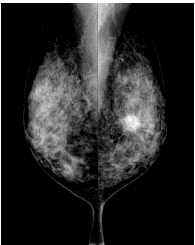

「マンモグラフィ」は乳腺のX線検査です。乳がんをはじめ乳房にできる病気をほとんど見つけることができ、しこりとして触れないごく早期の乳がん(微細な石灰化)も発見できます。 X線を使いますが、その量はごくわずかでほとんど危険はありません。

マンモグラフィ検査は、乳房を挟み圧迫しながら撮影を行う検査です。

乳房を圧迫しながら薄く均一に広げることによって、乳房内をより鮮明に見ることができます。触ってもわからないような早期の小さながんや、非常に小さな石灰化*をみつけることができます。(*石灰化があるからといって必ずしも悪性とは限りません)

マンモグラフィでは、触診ではわからない小さながんを発見できます。

マンモグラフィによる腫瘤(左)と石灰化(右)